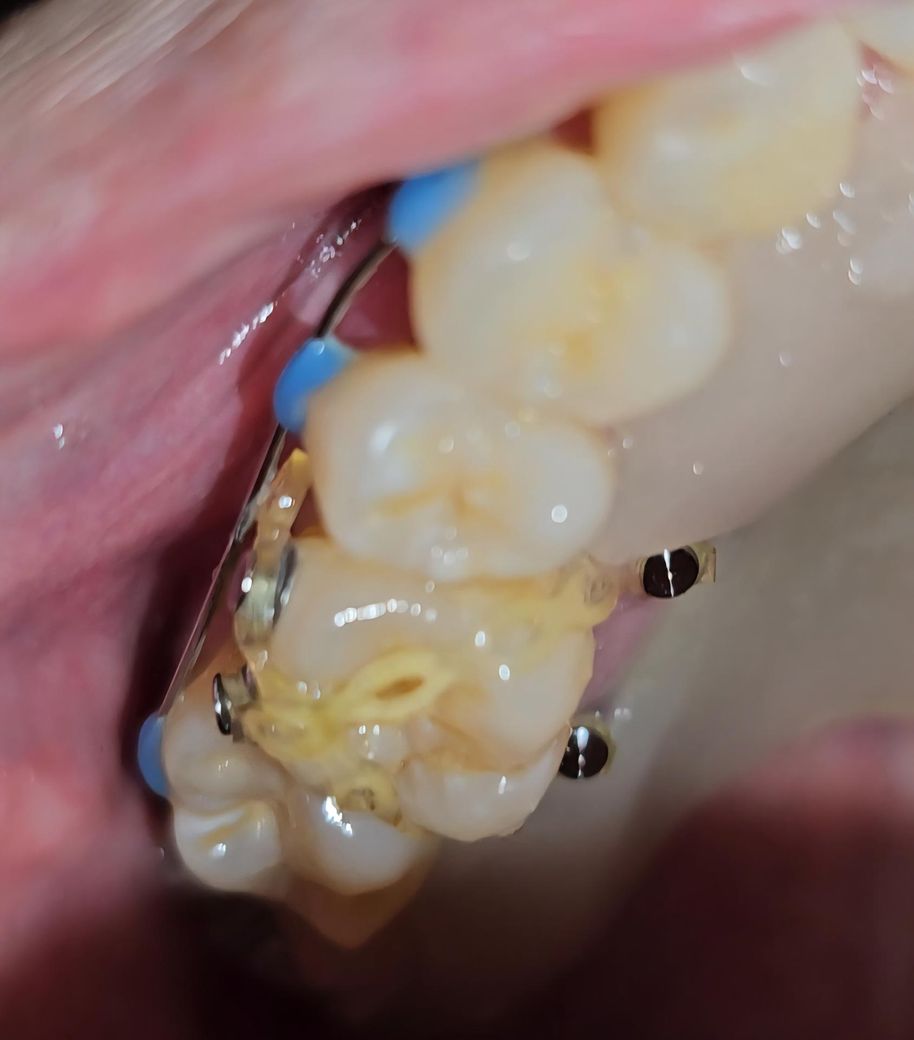

압하교정 중인 치아가 많이 돌아간거 같아요

입천장 안쪽에 스크류 두개 어금니 바깥쪽에 고정장치 두개 그리고 고무줄로 교정 중입니다.

3개월 차인데 압하는 조금 된거 같은데 어금니가 너무 돌아가서 이게 정상인지 궁금 해서 올립니다.

돌아가도 너무 돌아 간거같은데 어떻게 해야 될까요

• 1번 째 사진